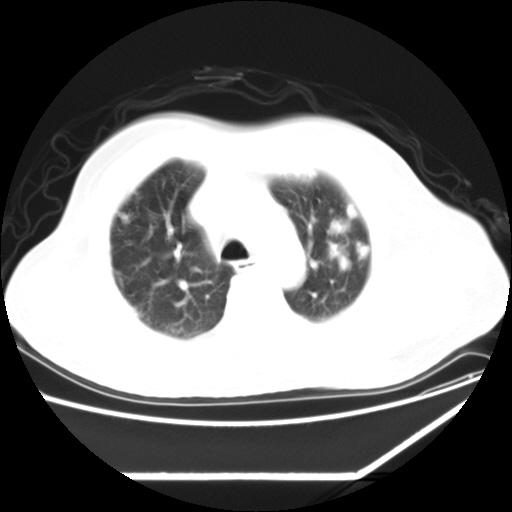

男,57,畏寒,发热

双肺多发结节样病灶,部分内见透光区,纵隔内见淋巴结肿大。结核临床如有畏寒,高热,白细胞增高首先考虑迁徙性肺脓肿(多是金黄色葡萄球菌感染)。

注意除外转移瘤。

双肺典型的亚急性粟粒性肺结核

双侧胸膜结核

1)考虑两肺感染性病变(金黄色葡萄球菌肺炎?);建议抗炎治疗后复查排除其他。2)双侧少量胸腔积液。